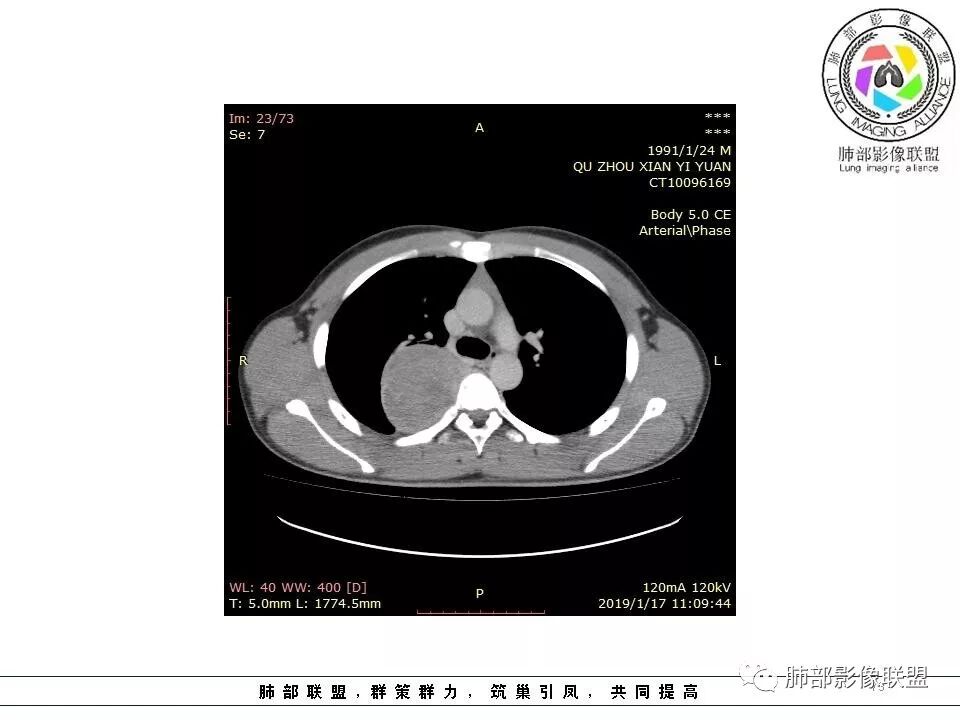

青年男性,间断胸痛;右侧脊柱旁可见一类圆形软组织密度影,密度欠均匀,增强扫描呈轻中度持续强化,邻近肺组织及肺动脉推移,可见肋间动脉供血,部分胸膜下脂肪可见,部分层面似见与右侧椎间孔相连。考虑后纵隔神经源性肿瘤。

青年男性,右侧脊柱旁软组织肿块,边缘膨隆,密度不均,临近肺组织受压、胸膜增厚,增强后动脉期呈不均匀强化,并可见肋间动脉供血,延迟期强化较均匀,定位肺外,首先考虑SFT,神经源性肿瘤待排

青年男性,右侧后纵膈肿块,有胸膜尾征,支气管被推压,定位肺外,脏胸膜?血供来自肺动脉及肋间动脉,增强后有强化,蛇纹征,考虑SFT,鉴别鞘瘤

右肺占位,跨越上叶后段、下叶背,边缘光滑,瘤肺界面清,见肺压缩缘(线样不张`强化),见胸膜尾征,胸膜下脂肪未见明显增厚,肋骨丶脊柱未见侵袭及受压,渐进性丶地图样强化,冠状位似见体循环供血

诊断:SFT(来源壁层胸膜?一般小于20%)

鉴别:神经源性(鞘瘤)、LCD、肉瘤丶孤立性间皮瘤

青年男性,右后上纵隔脊柱旁沟可见团状软组织影,边界清,密度尚均匀,推挤邻近肺组织,胸膜可见掀起,有肺动脉供血,增强轻度蛇皮样强化,纵隔淋巴结未见肿大,邻近骨质未见破坏,胸膜下脂肪间隙消失,考虑SFT孤立性纤维瘤可能性大,鉴别神经鞘瘤,节细胞瘤,建议活检。

青年男性,胸痛,右上纵膈脊柱旁肿块,形态光整规则,支气管被推移,临近的胸膜明显增厚,有胸膜掀起,增强后密度不均匀,可见蛇形血管征,血供似乎有两根血管供血,考虑SFT

边缘光滑,宽基底与胸壁相连,跨叶裂,叶裂稍前推,血管、支气管前移。

浅分叶

外上侧少量胸水

肋间动脉供血,强化尚均匀,逐步强化

1.右上胸内脊柱旁类圆形肿块,质地似乎比较坚实,密度稍显不均,但未显示明确的坏死。

如此密度形态的病灶位于肺边缘首先应当想到孤立性纤维瘤,可相邻胸膜未见明显的异常强化和胸膜方向延伸。

2.肋间动脉病供血也提示肿块来自后纵隔?